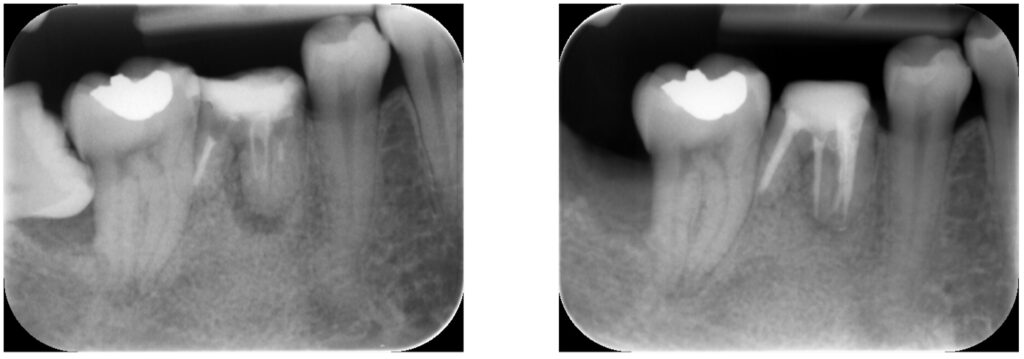

症例26:根尖性歯周炎

何もしてなくても痛い、腫れている、噛めない

根尖部の炎症の改善、再感染の防止を行いました。